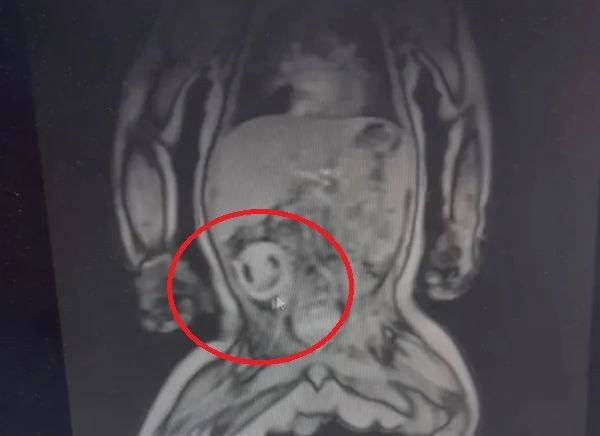

![생후 4개월 된 남아 뱃속에서 기생 태아가 발견됐다. 이 기생 태아는 머리카락, 눈, 척추 등이 발달했으며 마치 미소짓고 있는 듯한 모습이다. [사진=웨이보 캡처]](https://img4.daumcdn.net/thumb/R658x0.q70/?fname=https://t1.daumcdn.net/news/202311/10/KorMedi/20231110175109139akqa.jpg)

태어난 아기의 뱃속에 미소짓고 있는 얼굴...마치 외계인처럼 보이는 이것의 정체는 뭘까?

기생 태아 크기는 약 6cm로, 아이의 몸속에서 함께 자라 머리카락, 눈, 척추 등이 발달한 형태였다. 엑스레이 사진에서도 마치 웃는 듯한 모습이었다. 기생 태아는 약 1시간 30분의 수술 끝에 모두 제거됐으며, 아기도 현재 회복한 것으로 전해졌다.